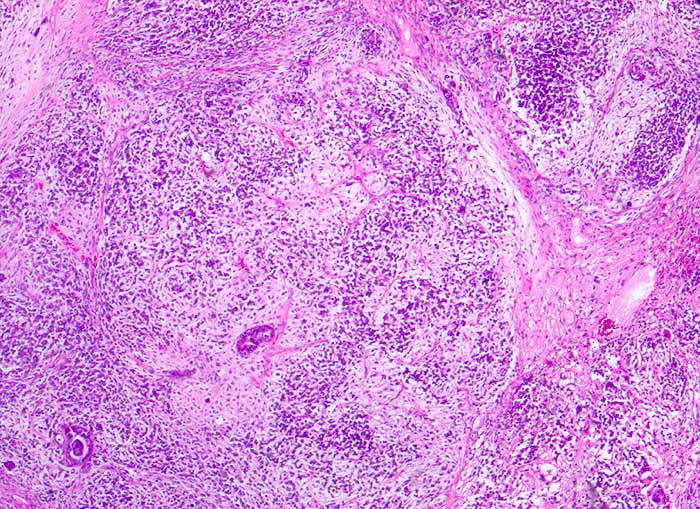

PathoPic ID 5386 - maligner Müller'scher Mischtumor des Ovars

maligner Müller'scher Mischtumor des Ovars

Karzinomatöse Drüsen in malignem mesenchymalem Stroma

Histologie

25